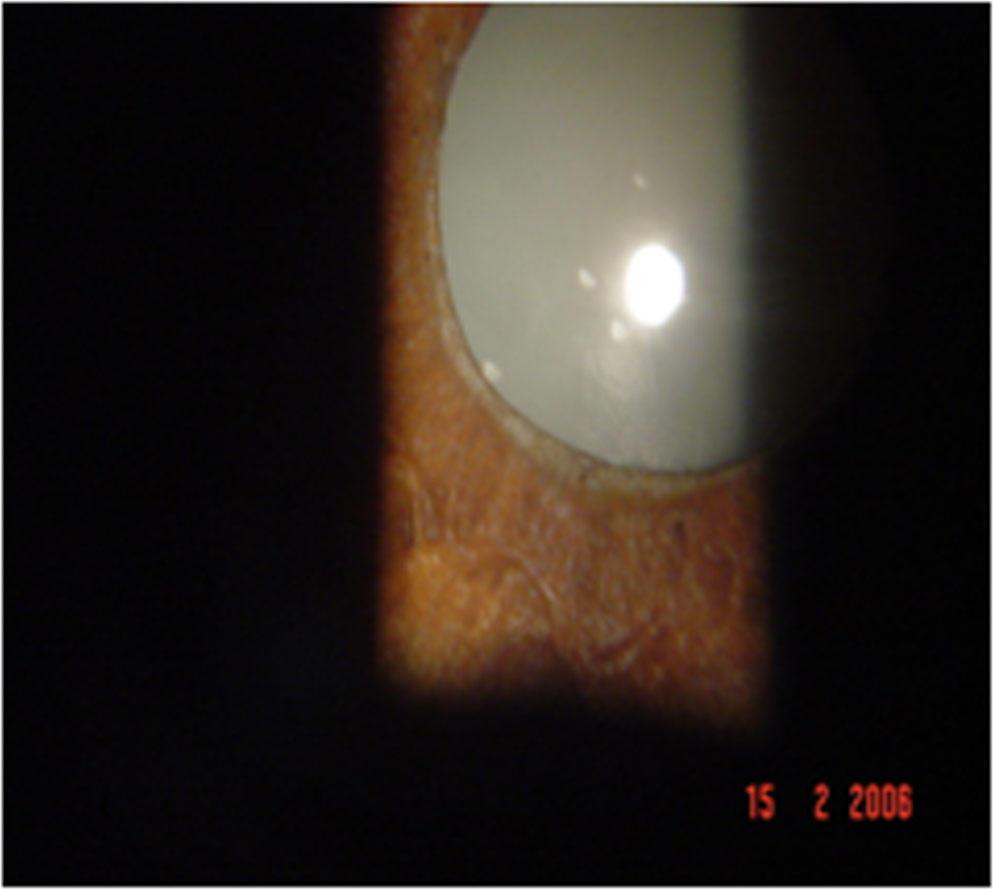

38% showed acute anterior uveitis and 62% showed chronic anterior uveitis. It was granulomatous in 83% with the predominant clinical feature being iris sphincter atrophy and dilated pupil with large mutton keratic precipitatesand anterior chamber cells and flare. 17 % of patients presented with a non- granulomatous iridocyclitis although that is not a usual presentation in uveitis. Cataract was noted in 33% of patients. On morphological evaluation, posterior subcapsular cataract was the most common feature and both senile and complicated cataract were seen. Several of our patients had dilated pupil due to iris sphincter atrophy. Vitritis was present in 3% of patients and was seen as grade 2 cells with vitreous haze. Fundus examination was normal in all patients. 12% of patients had scleritis of the nodular type. Those with scleritis showed resolution with topical steroids with no recurrence and a scraping was not performed on them. Treatment for iridocyclitis was 1% atropine eye drops,1% prednisolone acetate eye drops and oral steroids in the dose of 1mg per kg bodyweight In those with no resolution to this treatment for more than 3 weeks, an anterior chamber paracentesis was performed. RT- PCR performed on the aqueous humour of 12 patients with recalcitrant uveitis showed detection of DNA of M. leprae in 3 of them. A smear in these patients showed the presence of live and dead bacilli. Microscopy showed the typical morphology of fully formed live bacillus and beaded dead bacilli both existing in the same sample. After completion of treatment, the onset of uveitis in the paucibacillary type occurred within 1 year in 9% of patients, 2 years in 33% and within 3 years in 11%. Those with multibacillary leprosy had recurrence of uveitis after 3 years of completion of treatment. No patients had uveitis before that time period.

- Figure 3: Iris sphincter atrophy with dilated pupil

Figure 3: Iris sphincter atrophy with dilated pupil